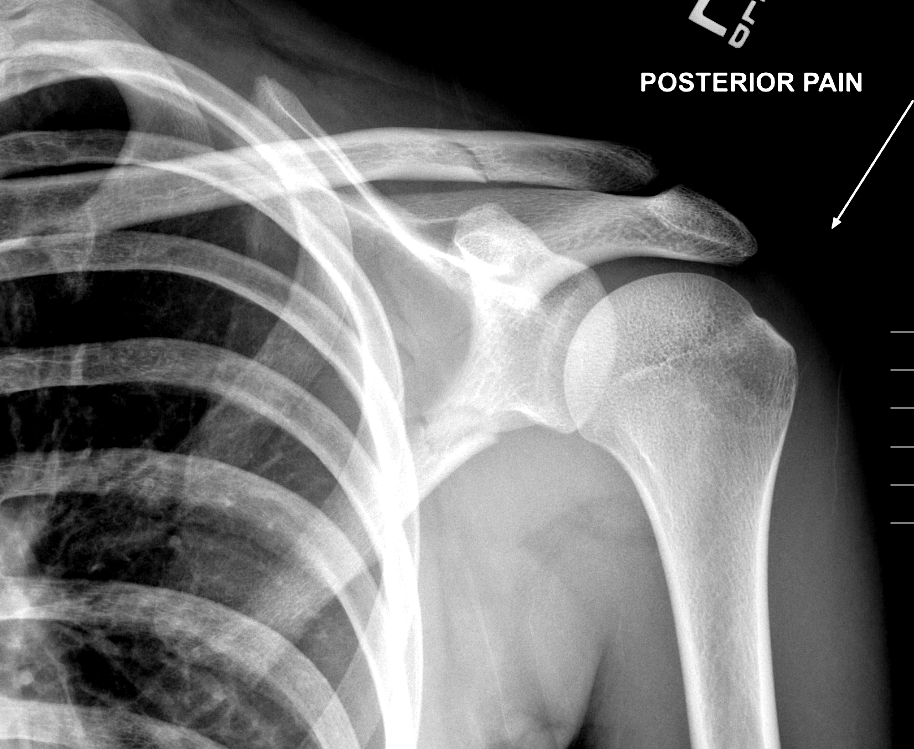

Info Images Findings Impression Reco/Acuity Case Images View Images / Launch Visage Case Notes History 2-month-old presents with decreased right arm movement, increased fussiness, and increased sleepiness for 2 days. Suspected non-accidental trauma. Exam Skeletal survey Prior Study none Dicom View Reference Material

Section 1 Submit Findings CB1550 Findings Skeletal Survey - Technique Check Skull AP/Lat Yes No Cervical and Thoracolumbar spine Yes No Chest X-Ray Yes No Ribs – Left/Right Oblique Yes No Abdominal X-Ray Yes No Pelvis with both hips Yes No Bilateral Humerus, Forearm, Hand Yes No Bilateral Femur, Tibia/fibula, feet Yes No Any additional lateral views of the extremities Yes No The exam is over or under penetrated. Yes No The exam may or may not be limited by overlying structures or soft tissues, body habitus, patient positioning, support devices, or motion. Yes No The area of concern is indicated by the patient, technologist, or care provider. Yes No The area of concern is included on the exam. Yes No Soft Tissues There is soft tissue swelling, indistinctness of fat/muscle planes, gas, or laceration in the area of clinical concern. Yes No There is an effusion, fat pad displacement, or fat fluid level. Yes No There is a radiodense or lucent foreign body. Yes No There are other densities, calcifications, post-surgical changes, or support devices in the soft tissues. Yes No Any support lines/tubes. Yes No Bone There is a break or interruption of the continuity of the cortical or cancellous bone. Yes No There is overriding of the trabeculae with apparent sclerosis. Yes No There is displacement of a fracture fragment. Yes No There is bowing of the bone in addition to the fracture at the apex of the bowed bone concerning for the greenstick. Yes No There is a spiral fracture of the leg concerning for toddler’s fracture. Yes No There is abnormal angulation or bulging of the cortical surface relative to the normal cortex which could be from a buckle or torus fracture. Yes No There is a displaced fragment which may be from avulsion by a tendon, ligament, or joint capsule or from a comminuted or other fracture. Yes No The stress trabeculae or other trabeculae of the cancellous bone are interrupted or otherwise abnormal. Yes No There is subperiosteal or endosteal reaction which could indicate a healing or subacute fracture or other abnormality. Yes No There is hard/soft callus formation. Yes No There is remodeling of the bone. Yes No There is a corner fracture or metaphyseal lesion that could be from nonaccidental trauma. Yes No There are multiple fractures of different ages. Yes No There are vertebral body/spinous process fractures. Yes No There are rib fractures. Location - posterior or lateral. Yes No There is scapular/sternal fracture. Yes No There are fractures of the digits. Yes No There are wormian bones. Yes No There are intrasutural bones. Yes No There is metaphyseal abnormality (lucencies, increased density, erosion) which may be from something other than injury such as stress, metabolic disease (e.g. rickets with loss or distortion of the zone of the provisional calcification), neoplasm (e.g. leukemia), heavy metals, inflammation, or infection. Yes No There are metaphyseal spurs. Yes No There are bony deformities involving multiple bones. Yes No The bones are gracile. Yes No There are non-healing fractures. Yes No There is/are focal or multifocal lytic/lucent, blastic/sclerotic or mixed density lesion(s) or other abnormality. Yes No Overall bone density is increased or decreased with or without thinning or thickening of the cortical or cancellous bone. Yes No Growth plates, ossification centers, apophyses The growth plate(s) is/are abnormal. Yes No There is widening of the physis from a fracture with or without displacement of the epiphysis (Salter-Harris I). Yes No There is a fracture through the physis which then extends into the metaphysis with or without angulation or displacement (S-H II). Yes No There is a fracture through the physis which then extends into the epiphysis and is intra-articular, with or without angulation or displacement (S-H III). Yes No There is a fracture through the metaphysis, physis, and epiphysis which extends into the joint space with or without angulation or displacement (S-H IV). Yes No There is narrowing of the physis from a compression fracture (S-H V). Yes No The apophysis, epicondyle, secondary ossification center, or accessory ossicle is displaced or otherwise abnormal. Yes No The ossification centers are underdeveloped. Yes No Joints and alignment There is an effusion, fat pad displacement, or fat fluid level. Yes No The epiphysis or subchondral bone is fractured, interrupted, flattened, compressed, impacted, displaced, or otherwise abnormal. Yes No There is an intra-articular loose body or chondrocalcinosis. Yes No The joint is widened, narrowed, dislocated, malaligned, or incongruent. Yes No There is pseudoarthrosis. Yes No Other findings There are developmental changes or other anatomic variants or other existing conditions that may or may not be contributing to symptoms which can or should be further evaluated non-emergently or are otherwise incidental. Yes No The remainder of the exam is abnormal for age. Yes No The lungs show focal airspace opacity. Yes No There is pneumothorax. Yes No There is organomegaly. Yes No There is intra-abdominal calcification. Yes No There is displacement of the bowel loops. Yes No There is free intraperitoneal air. Yes No The bowel loops are dilated/obstructed. Yes No There is paraspinal soft tissue abnormality. Yes No